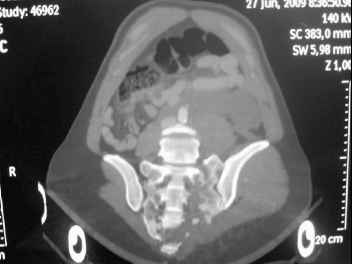

I'm posting this case on behalf of Dr. Pedro Caba, he is unable to post but able to read. 41 yo female , fall from 10 meters five days ago. Hemodynamically unstable on admission treated by angio and embolization and skeletal traction, with no external support. No associated injuries. Based on CT scan the pt has a both column fracture with conminuted dome and displaced anterior column and a sacral Denis 1 fracture with a displaced left ala. I think the best approach for the acetabular fracture is ilioinguinal with Smith-Petersen extension but don't know exactly the sequence . Will you start with the sacral fracture? Which technique? Thanks in advance Pedro Caba Unidad de Trauma Hospital 12 de Octubre Madrid Spain

This patient has extensive and complicated skeletal injuries...much more data (such as additional relevant images and clinical information regarding the soft tissues and overall patient status) would help us formulate an informed plan.

The sacral pattern alone is quite difficult and seems to be some version of an H-pattern, but I can’t tell from these films.

General condition is fine except for an intractable pelvic pain, no associated injuries (only ankle fracture), no sciatic nerve injury.

The soft tissues are also in mild condition, buttock hematoma and probably a Morel-Lavalle. I send some more CT images. There are some conminution in the posterior column (I don’t have images now). The patient is scheduled for surgery next Monday. The plan is percutaneous sacral fixation and then ilioinguinal approach .